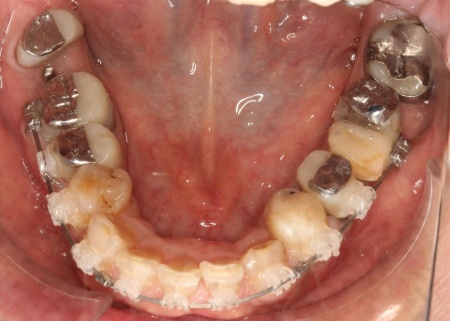

拝見したところ、もともと左上の歯と左下前歯が欠損しているうえ、奥歯の欠損も進んでいたため、噛み合わせが低くなっていました。

奥歯が噛み合わない状態になったことで、上前歯が前方に押し出され、出っ歯のようになっています。

また、下の歯は歯根だけが残る「残根」もあり、全体的に噛み合わせが不安定です。

さらに食いしばりの習慣があることから、残っている歯や顎関節に過度な負荷がかかっていると考えられます。